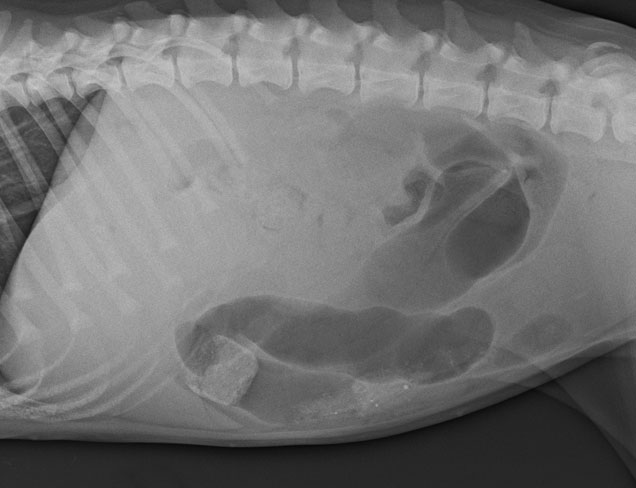

Nova the 5-month-old dog was brought into the RSPCA for treatment and care. She hadn’t eaten for days, had diahorrea, a temperature, white gums and was very lethargic. Something was clearly very wrong. X-rays revealed a corn cob lodged in Nova’s intestines! Although her prognosis was touch and go, she was one lucky puppy to have survived. After successful surgery to remove the corn cob, lots of medication and care, Nova made a full recovery and was adopted into a loving home.